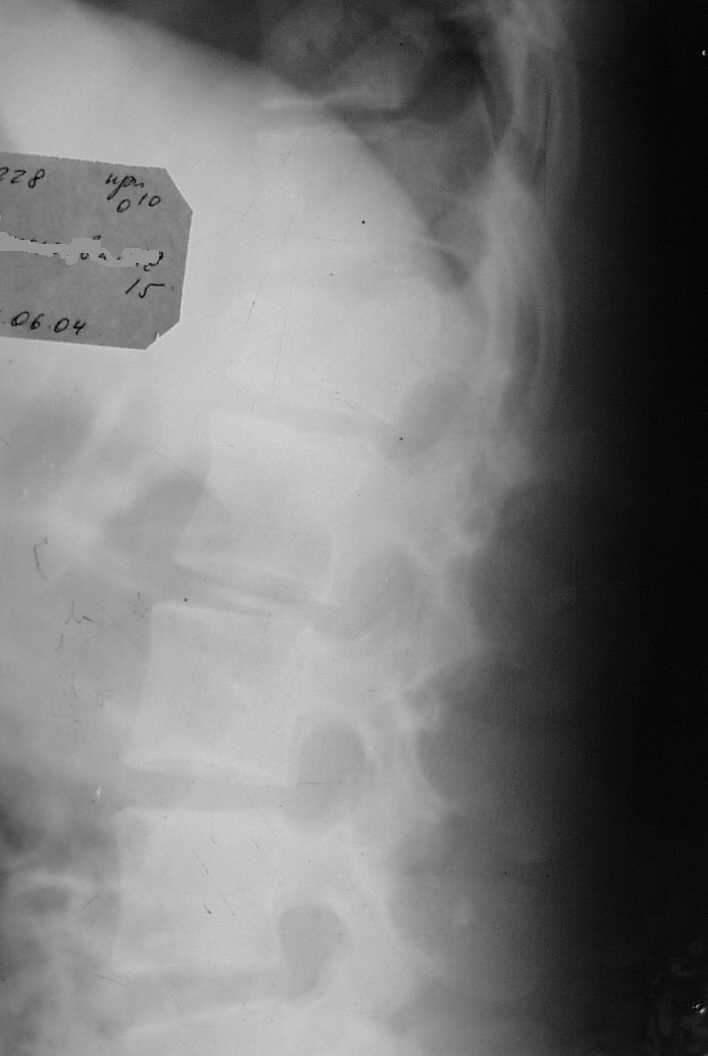

В травматологическое отделение поступила девочка 15 лет, после осмотра нейрохирургом с диагнозом Компрессионный перелом L1 Травма от 12/06-04 падение со скалы. Отделение не занимается оперативным лечением травм позвоночника. Нейрохирурги отправляя больную в дежурный стационар рекомендовали консервативное лечение.На момент осмотра и на настоящий момент неврологических растройств нет,девочка активно занимается ЛФК по методике, находится на щите с реклинирующим валиком.Прошу помочь разобраться нужна ли операция,где её можно сделать,сколько это будет стоить и в какой период,если необходима операция её надо делать.R-снимки прилагаются.Заранее благодарен. С уважением.Землянский А.А.

Обратите внимание на грыжи Шморля.

Не круглая ли спина у девочки?

Нет ли у нее болезни Шейерманна-Мау?

Компрессия конечно приличная, но такие переломы довольно успешно лечатся консервативно по методике Гориневской-Древинг с реклинирующим валиком под

место перелома при условии, что нет неврологической симптоматики.

Для решения вопроса о тактике лечения необходимо наличие компьютерной томографии (КТ).Если по ее данным определяется наличие вертебро-медуллярного конфликта, даже 1 степени, то при такой величине локальной кифотической деформации стоит провести оперативное лечение - транспедикулярную фиксацию конструкцией "Синтез", что позволит максимально полно устранить имеющуюся деформацию, произвести закрытую декомпрессию, надежную стабилизацию. Кроме того, это позволит не позднее чем через 2 недели активизировать больную, т.е. разрешить ходьбу в корсете. Если вертебро-медуллярного конфликта нет, то тогда возможно консервативное лечение на реклинаторе не менее 1 мес, затем консервативное лечение - массаж, магнит, электростимуляция мышц спины и т.д.

Показанием к оперативной стабилизации поврежденного сегмента позвоночника является нестабильный характер перелома в сочетании с неврологическими расстройствами или без таковых. Косвенно по обычной Рг грамме можно оценить стабильность по величине компрессии тела позвонка: если более 50%, то наиболее вероятно вовлечение задней колонны сегмента, соответственно, перелом расценивается как нестабильный и нуждается в транспедикулярной фиксации. Хотя выбор только задней стабилизации при компрессии, превышающей 50% высоты тела позвонка кажется спорным и спинальные хирурги сочетают заднюю фиксацию с передним корпородезом.

В данном случае похоже, что степень компрессии менее 50%,поэтому при отсутствии неврологических расстройств нейрохирурги от оперативной фиксации позвоночника отказались. Что бы ясно представлять себе характер повреждения неплохо бы было сделать КТ Т12-Л1 и если дужки и суставные отростки не повреждены, то вполне можно обойтись и без хирургии.